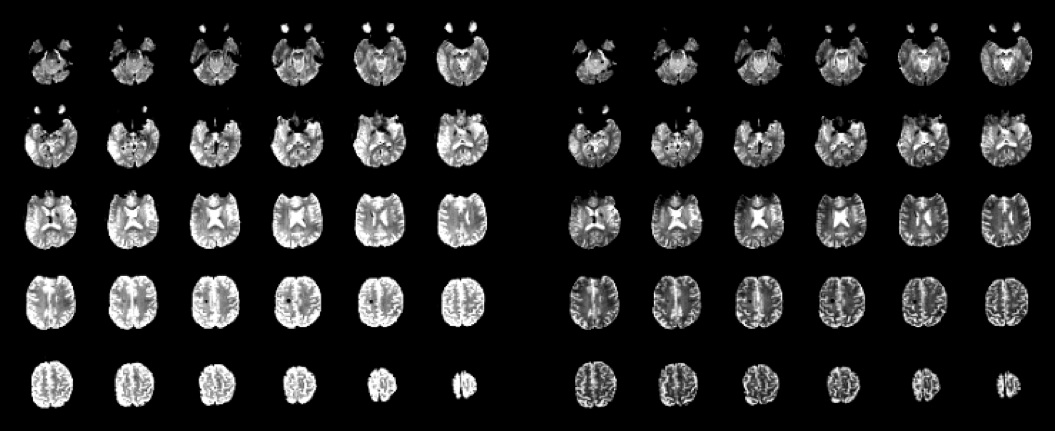

Below are EPIs acquired from a volunteer. (Please ignore the small black spot. It's benign and has been checked out, the subject is fine. We refer to it as his "internal fiducial.") As with the phantom images presented in the previous section, I set the gray scale intensity separately for each block of EPIs, to accentuate the Rx field heterogeneity before (left) and after (right) normalization:

![]() |

| 12-channel head coil receive patterns before (left) and after (right) a prescan normalization. (Click to enlarge.) |

| 32-channel head coil receive patterns before (left) and after (right) a prescan normalization. (Click to enlarge.) |

As expected, the results from a brain support the prior observations made in the phantom data. The 12-channel EPIs are more homogeneous than those obtained with the 32-channel coil without prescan normalization. It's difficult to make out much receive field heterogeneity in the raw 12-channel images now, because anatomical contrast dominates. We know it's there, though, even if it's difficult to see by eye. How? Because the prescan normalized images are different, and flatter!

The 32-channel coil data clearly benefits a great deal from prescan normalization. But there is more residual heterogeneity in the normalized images from the 32-channel coil than from the 12-channel coil. The prescan normalization is helping, but it's not a perfect fix.